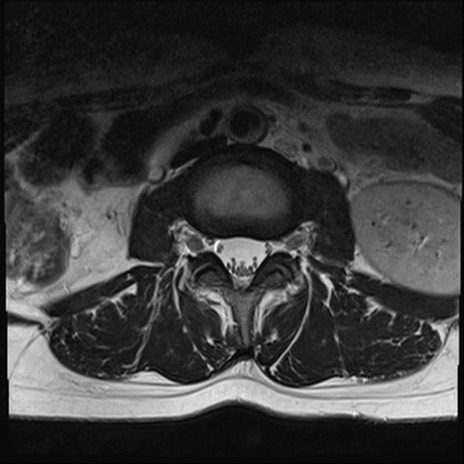

【整形】TIPS症例4 腰椎MRI T2WI(横断像)

腰椎MRI

横断像と矢状断像